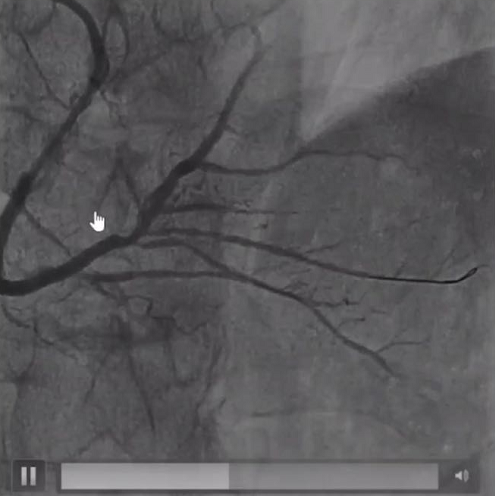

山东第一医科大学第二附属医院靳凤琳教授分享了一例小球囊在钙化病变中的应用。患者为一名因ACS入院的女性患者,超声心动图提示前壁运动幅度减低;冠脉造影示LAD自近段闭塞,LCX近段节段性狭窄40%,RCA近中段弥漫性狭窄40%-50%,并向LAD提供侧支循环。

手术过程中,使用XT-R导丝反复尝试后成功通过闭塞段,但由于钙化负荷较重,即使是1.5*15mm的小球囊也无法通过,随后换用1.0*10mm Firefighter™球囊自近段钙化病变及中段扭曲处反复进行高压扩张,后成功送入预扩张球囊进一步治疗。

LAD自近段闭塞

球囊预扩张后

复旦大学附属中山医院钱菊英教授针对该病例讲到对于通过性较差、无法旋磨的病变,小球囊掘进技术可以为后续处理提供良好的通过条件。这一过程除了需要术者高超的技术,当然也离不开合适的器械;微创®冠脉的Firefighter™球囊外径小且耐高压,正是一项不错的选择。